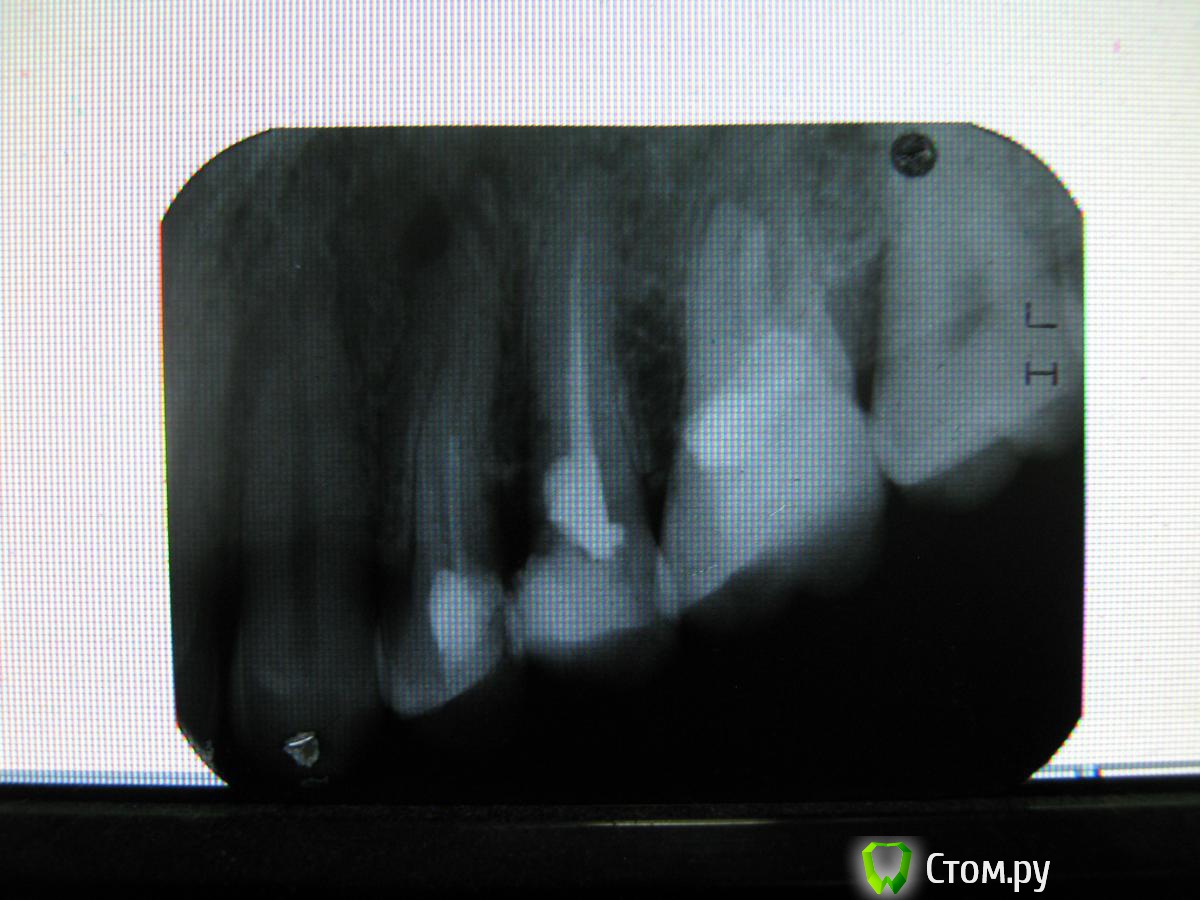

Kolchanov Опубликовано 9 марта, 2014 Поделиться Опубликовано 9 марта, 2014 как-то так 2 Ссылка на комментарий

Scrabble Опубликовано 9 марта, 2014 Поделиться Опубликовано 9 марта, 2014 (изменено) Нет никакого лечения солёной водой. Каналы зуба надо расширить, помыть и временно запломбировать. Потом каналы запломбировать на постоянно-герметично и до верхушек. Потом сделать вкладку и коронку. Не быстро. Не совсем дёшево. Четвёртый зуб тоже требует Вашего внимания в ближайшее время. А в пятом не исключена перфорация в коронковой части корня зуба+отсутствие тканей зуба мезиально под десну(на контакте с четвёртым) Изменено 9 марта, 2014 пользователем Scrabble 1 Ссылка на комментарий